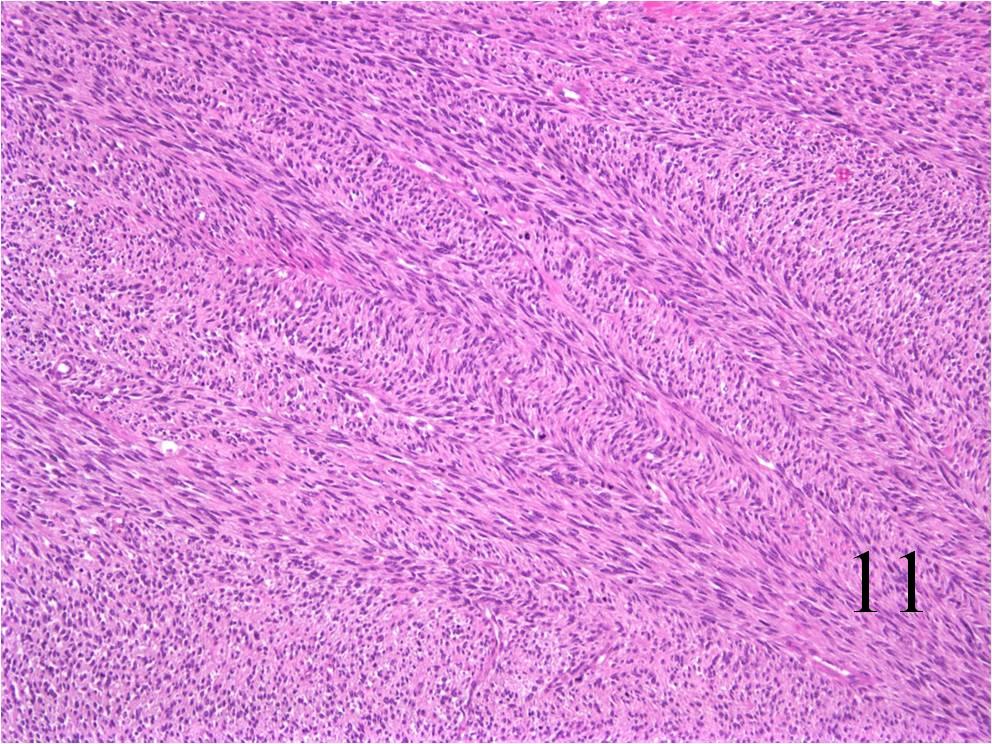

- Pleomorphic:

- Essentially identical to pleomorphic MFH

- Admixture of spindle-shaped, pleomorphic polygonal, round cells

- Arranged in fascicular, storiform, and patternless pattern

- Nuclei is large, oval-round, and multiple.